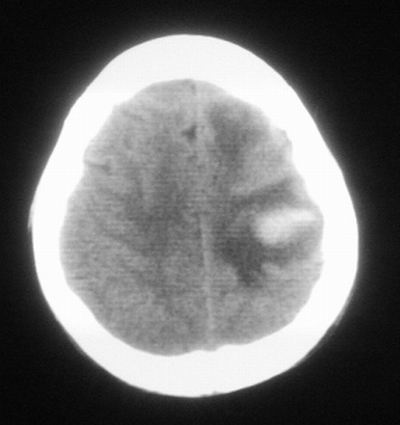

治疗三天后复查ct片示:

治疗三天后复查ct:除左侧额顶叶血肿外。左侧额叶另见片状低密度灶,密度不均匀,境界不清;考虑脑梗塞。

左侧额顶叶血肿伴出血后梗塞!

低密度区应该不是梗塞而是水肿区,建议进一步检查排除占位